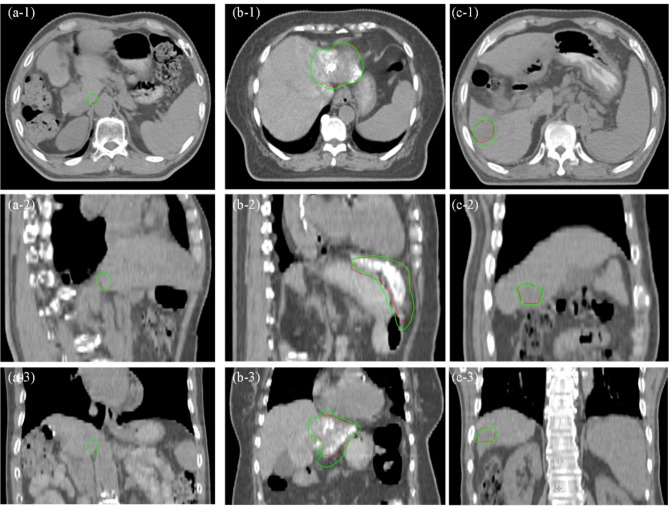

Methods: Twenty patients receiving radiotherapy for liver cancer were enrolled. Each patient underwent contrast-enhanced planning CT (free-breathing), contrast-enhanced T1-weighted (free-breathing), T2-weighted (gated) 3D-MRI, and low-quality 4D-MRI using the time resolved imaging with interleaved stochastic trajectories volumetric interpolated breath-hold examination (TWIST-VIBE) sequence. A dual-supervised deformation estimation model was used to generate a 4D deformable vector field (4D-DVF) from 4D-MRI data, and the prior images were deformed using this 4D-DVF to generate multi-parametric 4D-MRI. Assisted by 3D-MRI and multi-parametric 4D-MRI, target contours were performed on the planning CT, resulting in the generation of Target_3D and Target_4D. Clinical plans, Plan_3D and Plan_4D, were designed based on these contours respectively. To explore the dosimetric variations resulting from different contours without re-optimization, Plan_3D was directly applied to Target_4D, and Plan_4D was applied to Target_3D to generate Plan_3D' and Plan_4D' respectively. Target volume, contours, dose-volume histograms (DVHs), conformity index (CI), homogeneity index (HI), maximum and mean dose to organ as risks (OARs) were compared and evaluated.

Results: Mean volume differences between Target_3D and Target_4D were 2.76 cm3 (standard deviation [SD] 3.42 cm3) in the caudate lobe, 181.54 cm3 (SD 68.50 cm3) in the left hepatic lobe, and 26.08 cm3 (SD 20.52 cm3) in the right hepatic lobe. Mean and SD of CI and HI is 1.02 ± 0.04 and 0.108 ± 0.02 in Plan_3D, 1.02 ± 0.01 and 0.107 ± 0.01 in Plan_4D. There were no statistically significant differences in OAR doses between Plan_3D and Plan_3D', between Plan_4D and Plan_4D'. However, a statistically significant difference in target dose was observed between Plan_3D and Plan_3D' (P = 1.47 × 10⁻⁷) and between Plan_4D and Plan_4D' (P = 0.013). Plan_3D' meets 100% of the prescription dose covering mean 77.89% (SD 10.13%) of the Targeted_4D volume, while Plan_4D' covered mean 94.17% (SD 3.12%) of the Targeted_3D volume.

Conclusions: 3D image-guided target delineation may be more likely to underestimate target volume and compromise dose coverage, suggesting that using multi-parametric 4D-MRI can provide more precise target contours and enhance target dose coverage.